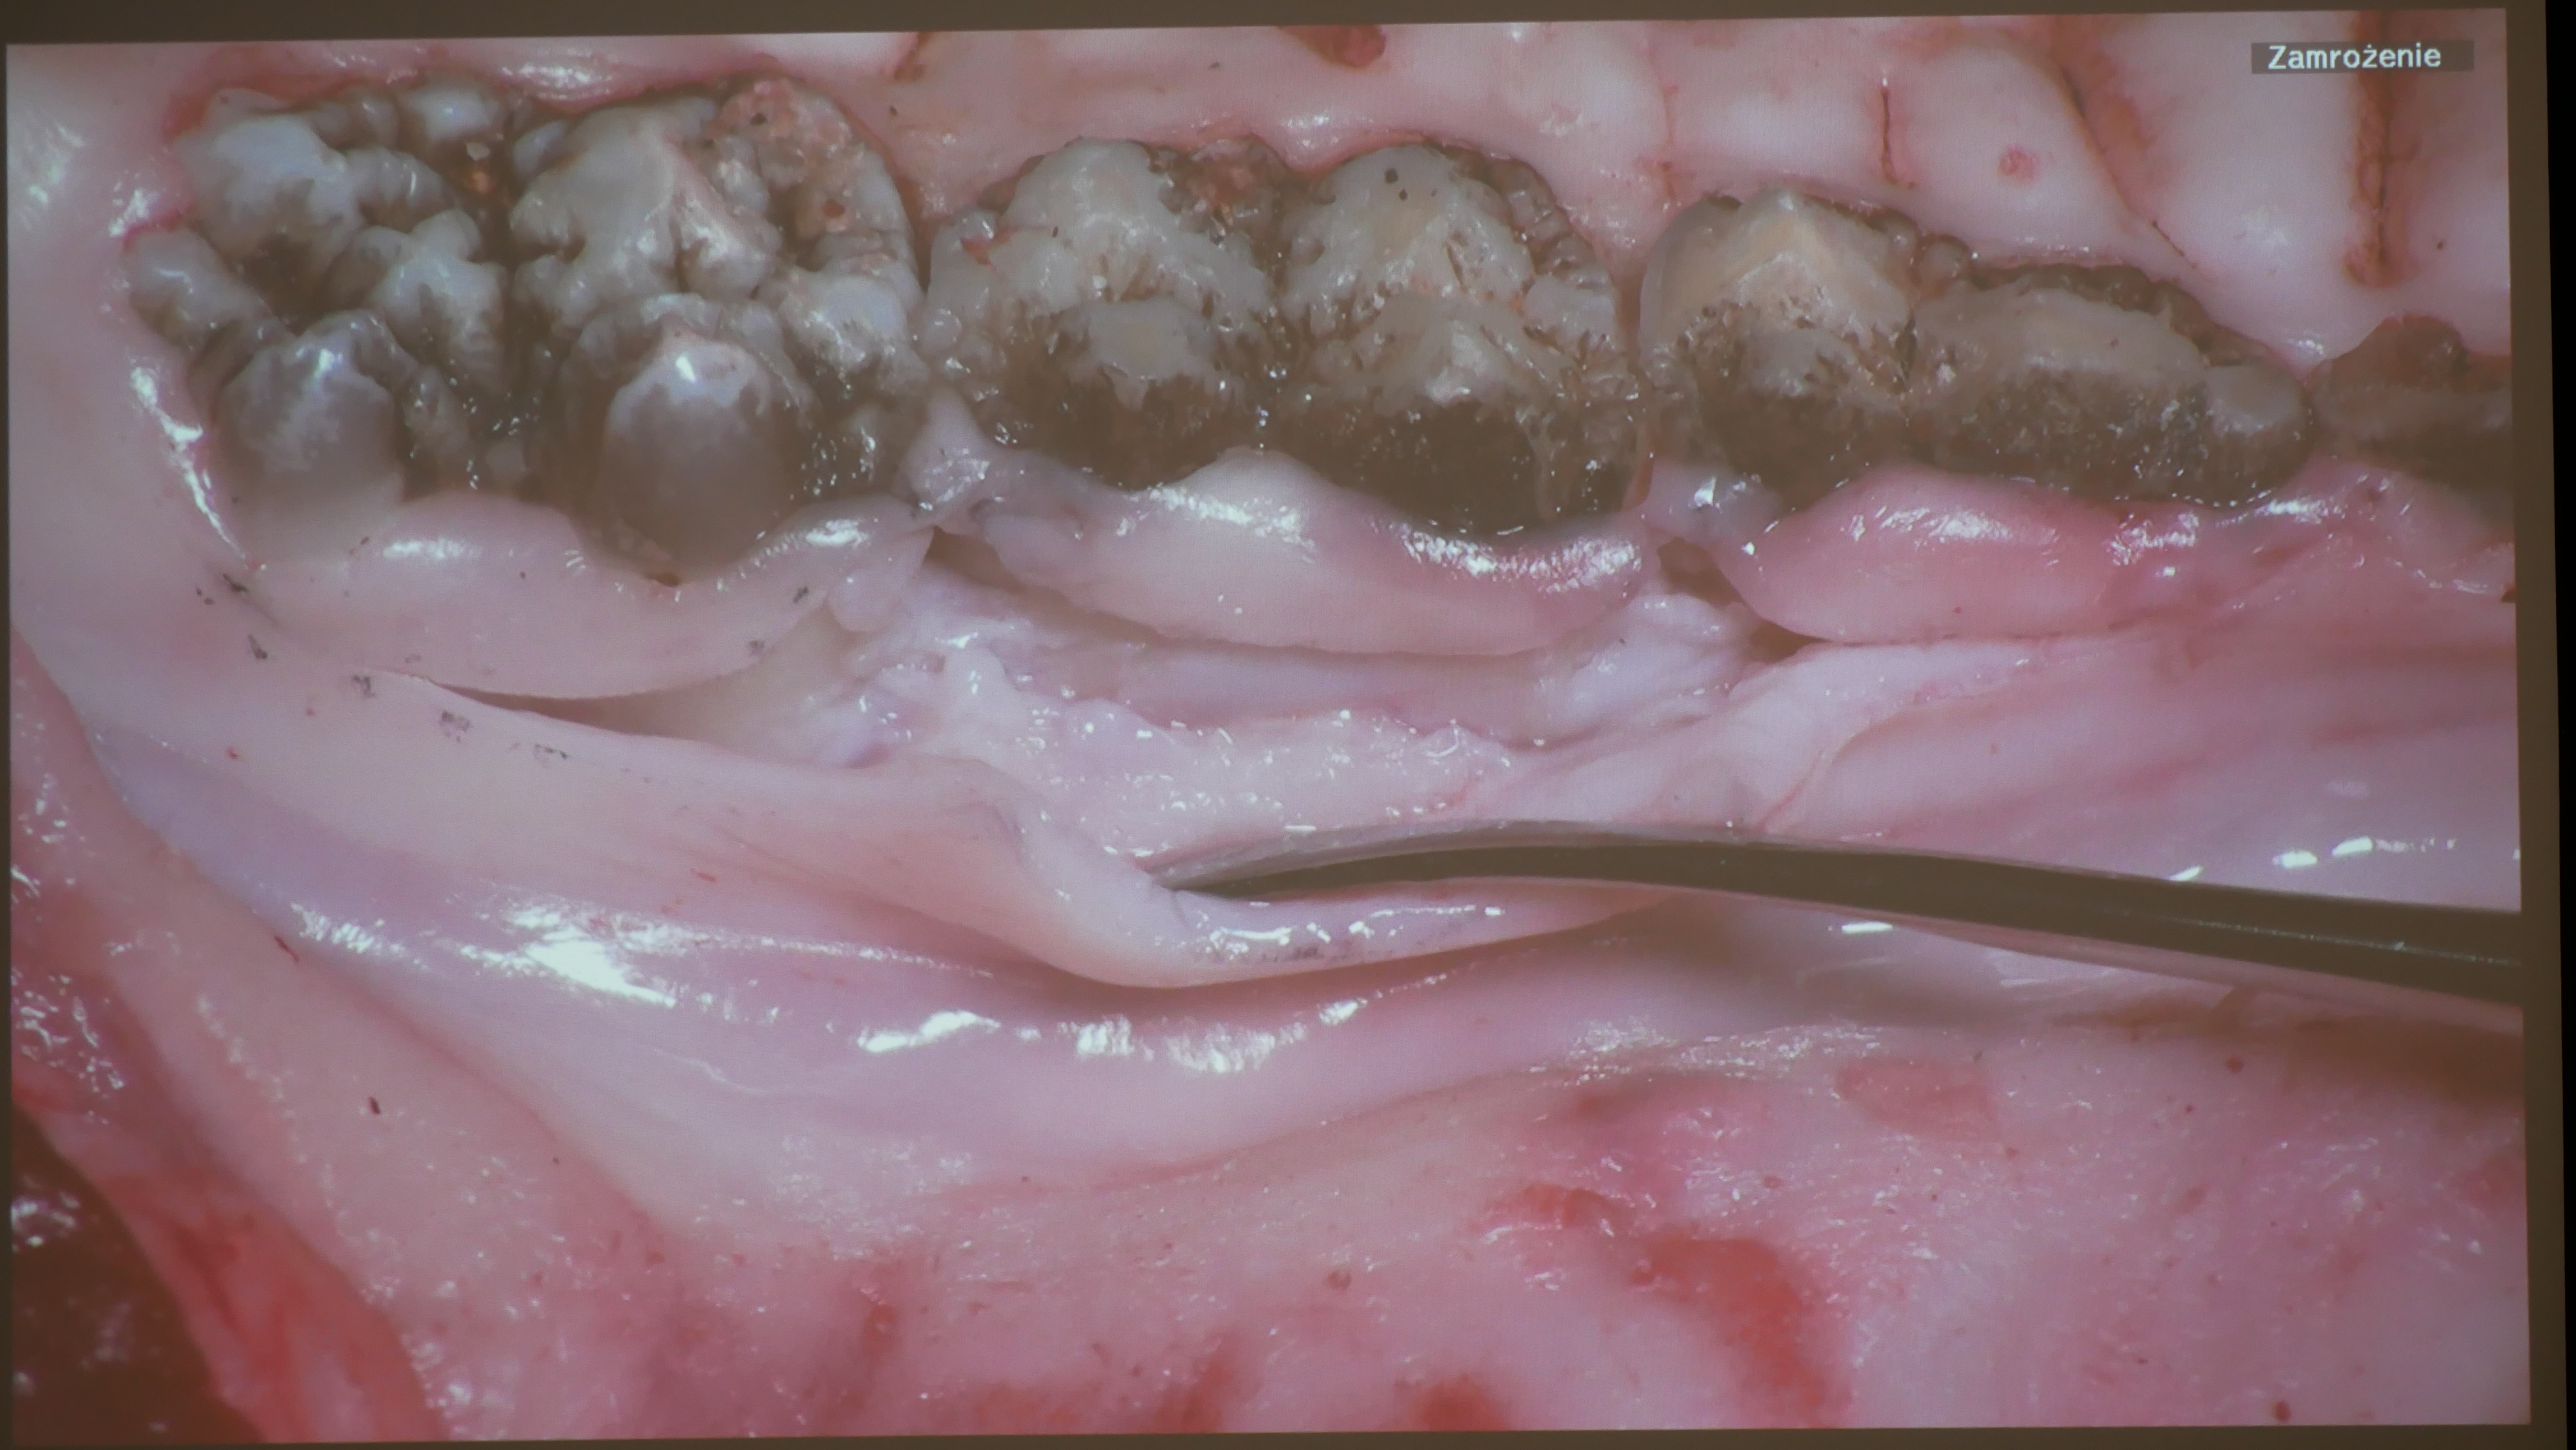

Terapia resekcyjna [19-21.01.2023]